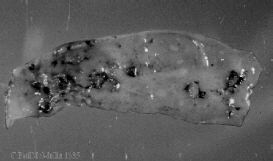

- Deep ulcers throughout intestine, but mainly ileum and caecae, which may coalesce and may be round or lenticular.

| Figure 35. Wall of the caecum of a chicken suffering from ulcerative enteritis |